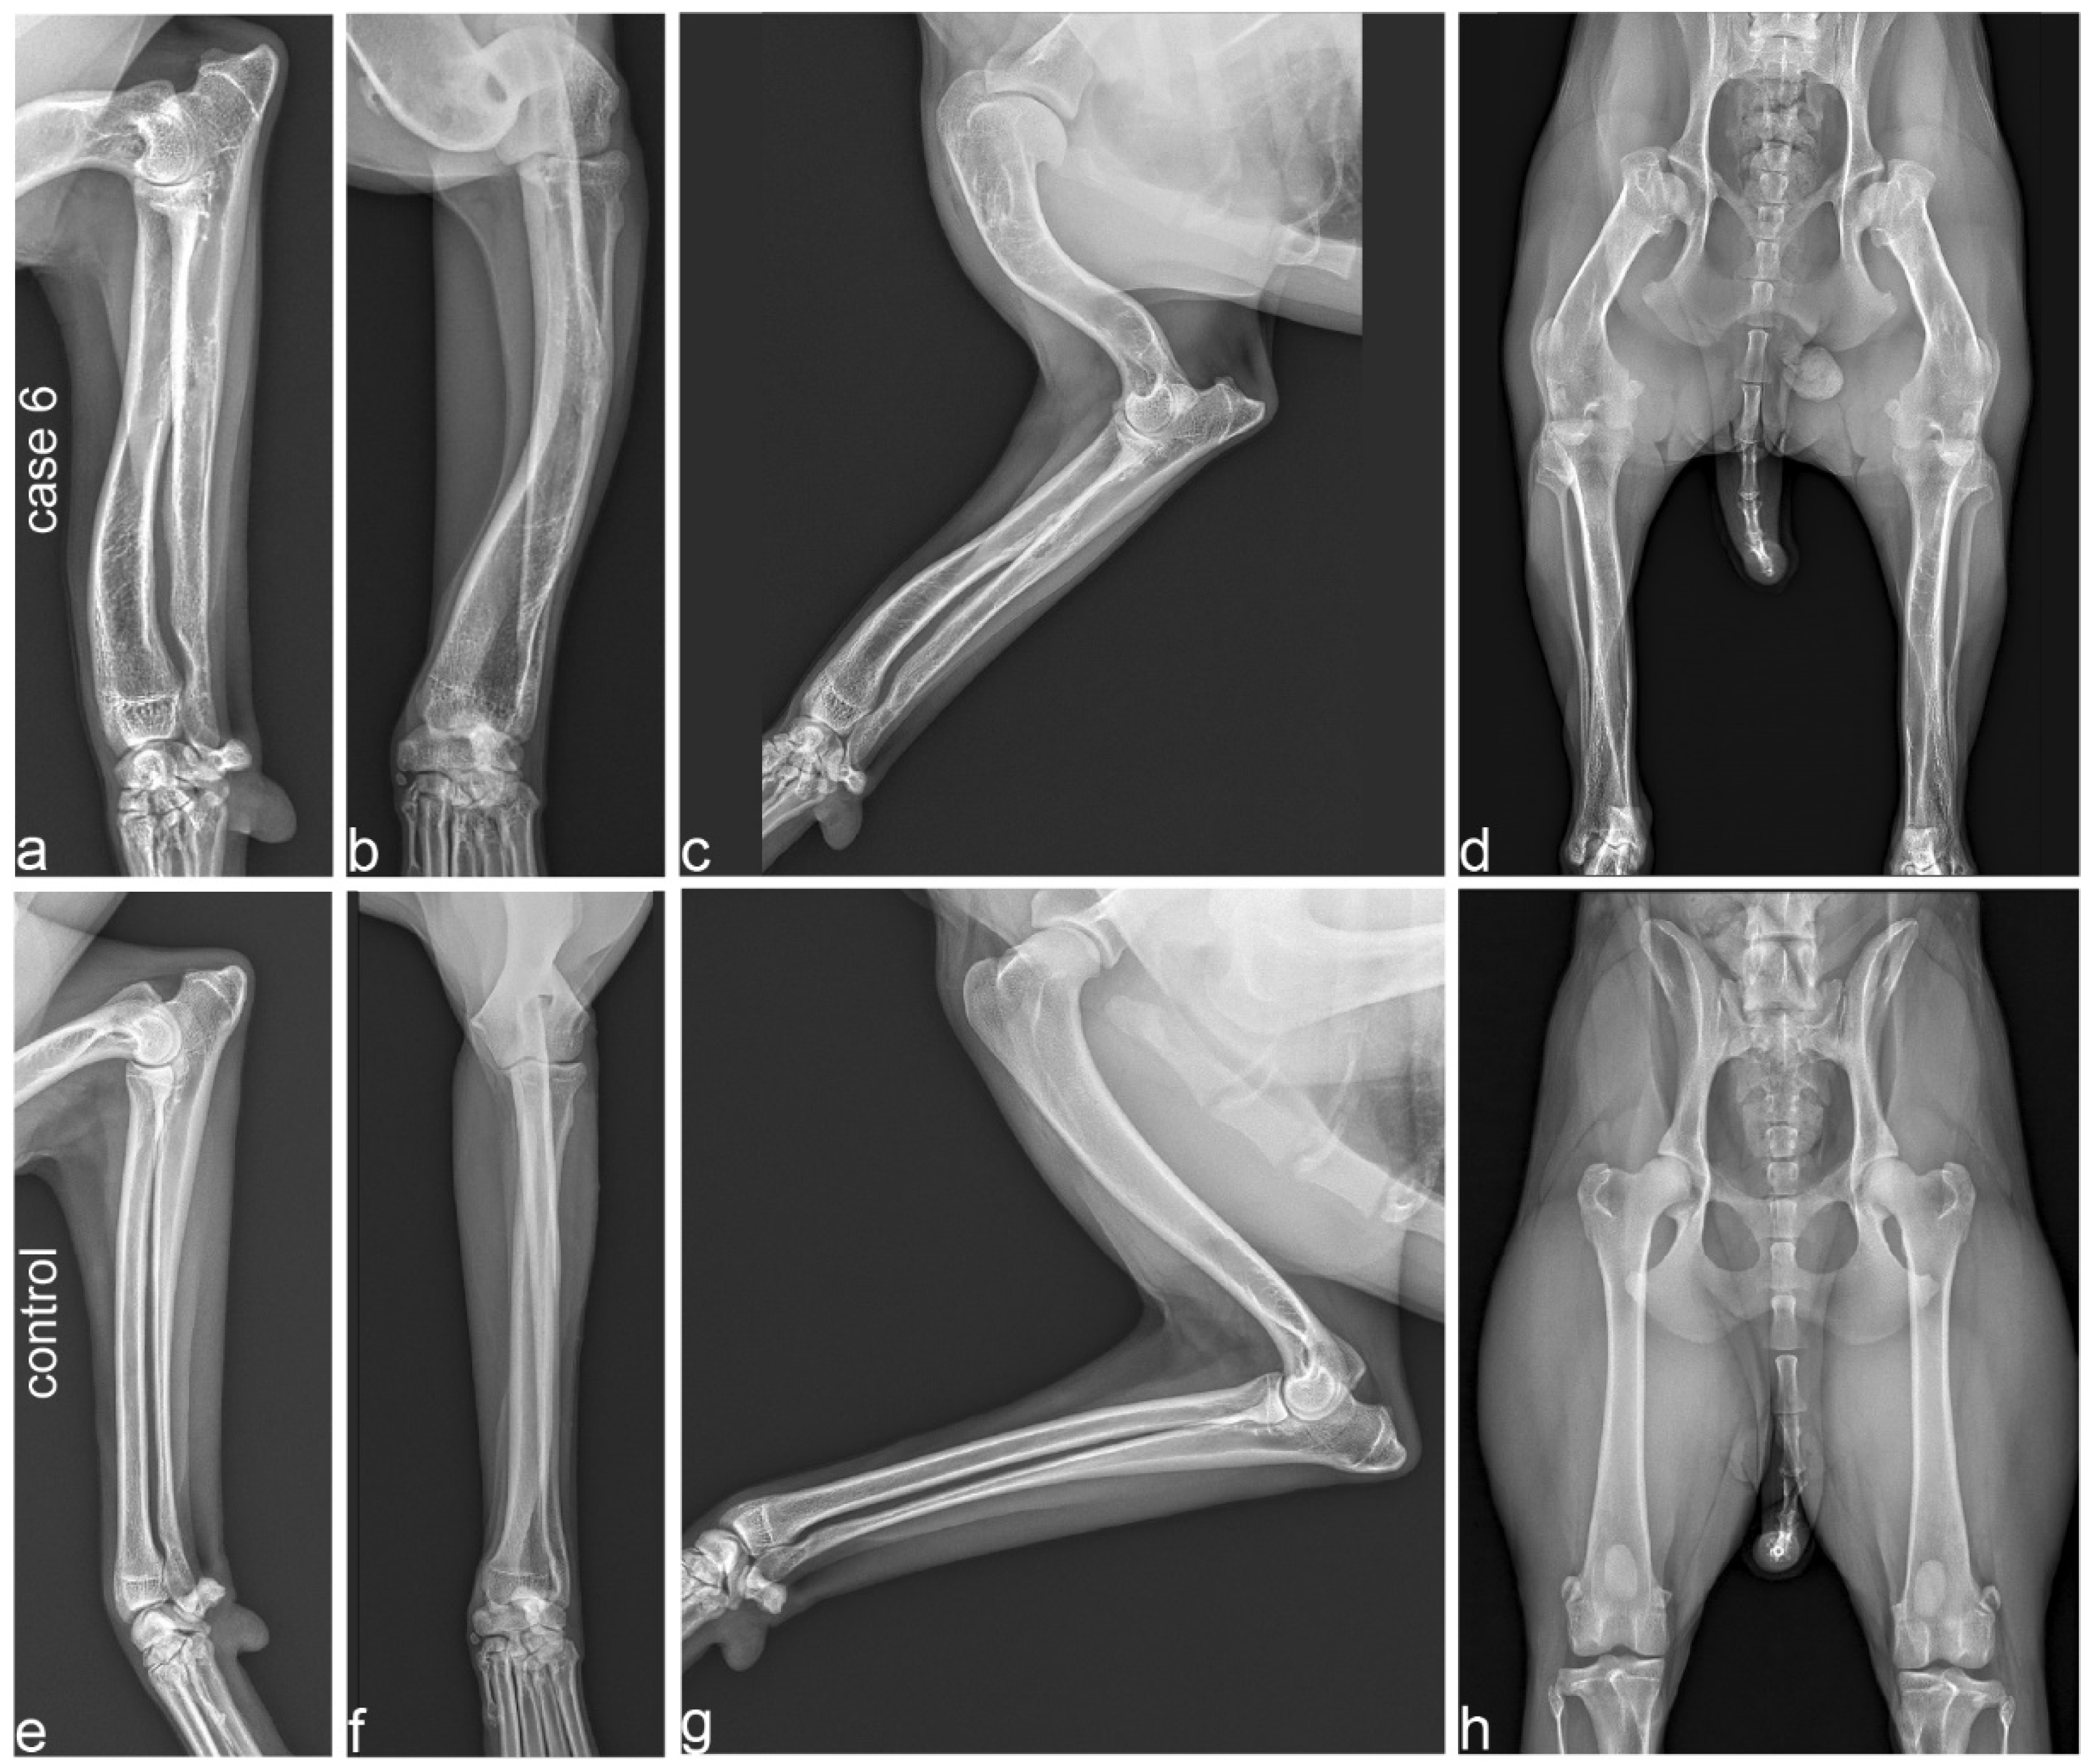

3.2. Diagnostic Imaging